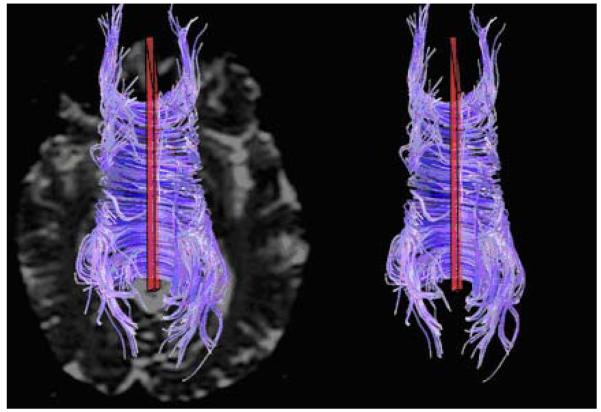

Figure 1 shows sagittal views of whole brain streamtube models for one healthy control and one patient with VCI. In the healthy control group, age was significantly correlated with NS, NNS, TL, TWLCL, and TWLFA (all r > −.50, p < .01) but not with average TL, NTL, NTWLCL, or NTWLFA. Thus, averaging streamtube length by the number of streamtubes or normalizing by intracranial volume appears to control for any association between the metric and age in healthy controls. In the VCI group, age was not significantly correlated with any of the metrics. Age was significantly correlated with average FA for the whole fiber model (r = −.48, p = .05) in the healthy controls but not in the VCI group.

Figure 1.

Whole brain streamtube models (sagittal view) for a 72-year-old healthy volunteer (left) and a 60-year-old patient with VCI (right). Note that the density of streamtubes is clearly decreased in the VCI subject despite the younger age. This observed difference provided the motivation for our metrics.

Figure 2 shows the TCF selection in a healthy control.

Figure 2.

Transcallosal fibers for a 48-year-old healthy volunteer showing placement of voxels-of-interest (in red) in axial view (top of image is anterior); for context, the left panel shows the fibers superimposed on a b=0 grey scale image.